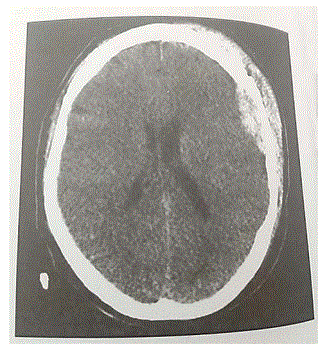

Um paciente de 25 anos de idade retornava de motocicleta para a própria residência, sem capacete, quando colidiu com um veículo ao ultrapassar o semáforo fechado. Foi atendido pelo resgate, que o levou ao hospital em prancha longa e colar cervical rígido. Na avaliação neurológica inicial pela escala de coma de Glasgow (ECGl), no local, encontrava-se com ECGl 14, com escoriações em tronco e membros superiores, além de ferida cortocontusa em região parietal D. Durante o transporte, apresentou rebaixamento do nível de consciência para ECGl 11 e vômitos. Ao chegar ao pronto-socorro, verifica-se que o paciente está com ECGl 7 e que não recebeu sedação durante a remoção. Exame físico: pupilas isocóricas fotorreagentes, em prancha com colar cervical rígido, ECGl 7, apresentando escoriações em tronco e membros superiores, além de ferida cortocontusa em região parietal D. Apresenta-se acianótico, afebril, hipocorado (+/4+), hidratado. FC = 50 bpm, PA = 196 mmHg x 120 mmHg, FR =24 ipm, Sat = 87%; apresenta movimentos ventilatórios bilateralmente, com roncos difusos à ausculta, abdome peristáltico, plano sem fácies de dor à palpação, sem massas e (ou) visceromegalias. MMII sem edemas, pulsos presentes. MMSS com escoriações superficiais, pulsos presentes.

Com relação aos achados, é correto afirmar que o paciente apresenta diminuição moderada do nível de consciência desde o momento do trauma até a avaliação no hospital, vômitos, hipertensão, bradicardia e eupneia (sinais clínicos de hipertensão intracraniana), mas ainda com pupilas isocóricas.